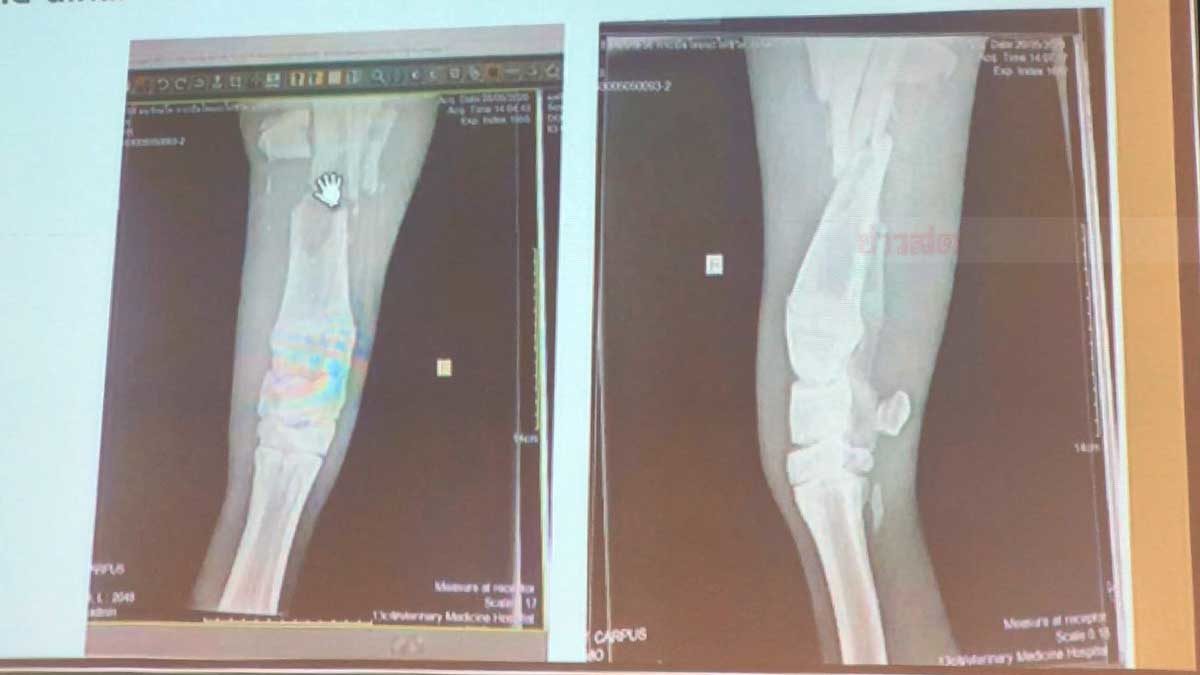

นสพ.กรฤต เปิดเผยว่า ควายเผือกตัวนี้เป็นเพศผู้ วัยรุ่น อายุประมาณ 2-3 ปี น้ำหนักตัวกว่า 400-500 กก. มีบาดแผลถูกรถชนจนขาหน้าขวาหัก ไม่สามารถลุกยืน และใช้ขาทั้ง 4 ข้าง ได้ สัตวแพทย์ได้ให้ยาฆ่าเชื้อ ยาแก้ปวด ตรวจเลือดหาความผิดปกติและภาวะแทรกซ้อน ซึ่งขณะนี้ได้มีการทำรักษาแผล และเข้าเฝือกให้กับขาหน้าขวาแล้ว กินหญ้าได้เล็กน้อย แต่พอที่จะดื่มน้ำได้บ้าง ซึ่งน่าจะมาจากอาการเจ็บปวดและความเครียดในสัตว์

เนื่องจากวัสดุอุปกรณ์ไม่แข็งแรงพอที่จะรับน้ำหนักสัตว์ที่มาก ซึ่งตอนนี้ได้แค่ทำแผล ใส่เฝือก ยกยืน เพื่อไม่ให้เกิดแผลกดทับ ซึ่งทำได้แค่ 2-3 ครั้ง ต่อวัน ครั้งละไม่เกิน 15-20 นาที หากมากกว่านี้จะส่งผลต่อพวกซี่โครง ปอด และอวัยวะภายในของสัตว์ได้